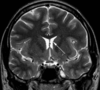

20

Q

A

4th ventricle

21

Q

A

basilar artery

22

Q

A

pineal gland

23

Q

A

nasopharynx

24

Q

A

left lateral ventricle trigone

25

anterior horn of right lateral ventricle

26

epiglottis

27

left internal carotid artery

28

left lobe of thyroid

29

left eustachian tube

30

left temporalis muscle

31

body of corpus callosum

32

right uncinate process

33

epiglottis

34

left posterior limb of internal capsule

35

tentorium cerebelli

36

right vertebral artery

37

left temporal lobe

38

venous sinus confluence

aka torcula herophili

39